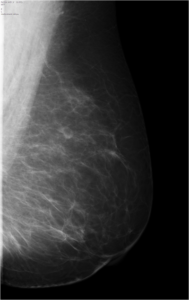

52 year old lady who underwent wide local excision for stage I breast carcinoma of right breast 7 years ago has presented for routine screening mammogram.

Ductal Cell carcinoma In Situ-DCIS RIGHT BREAST.(Comedo and cribriform type)

Craniocaudal and mediolateral oblique views of both the breast.Post operative scar is seen in the upper and outer quadrant of right breast.Pleomorphic calcifications,predominantly showing fine linear branching pattern( comedo pattern) is seen in segmental distribution with nipple convergence in the central right breast.